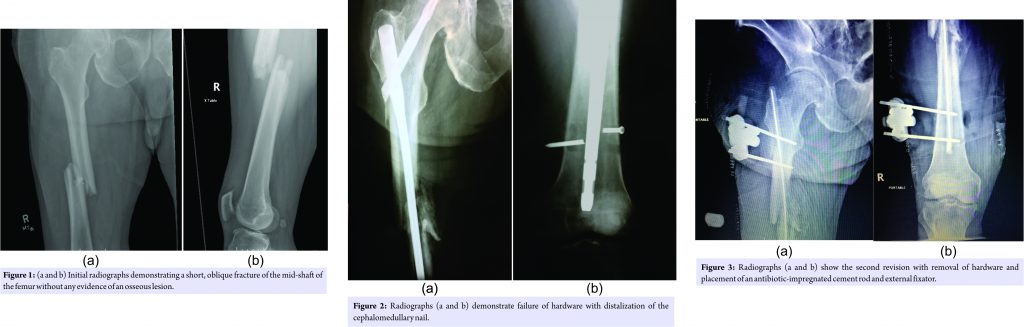

The patient was a 53-year-old Caucasian male presenting to the emergency department with a spontaneous pathologic right mid-shaft femur fracture that occurred while standing in the shower. He did not suffer any other injuries at that time. He admitted to a fall 3 weeks prior, in which he bumped his right thigh in a low energy mechanism during a near syncopal episode. It was ascertained that he had antecedent progressive right knee pain along with new-onset night sweats since the time of the incident. The patient denied any history of cancer or any other history of previous trauma. The patient had an extensive medical history including bipolar disorder, depression, chronic back pain, noninsulin dependent diabetes mellitus, and history of DVT and PE. In addition, he had a history of a previous episode of pneumonia, which was complicated by bacteremia and an empyema 1 month before at another local hospital. Records demonstrated that the blood and empyema cultures grew alpha-hemolytic streptococcus. At the time of admission, the patient had a temperature of 97.7° Fahrenheit and pulse of 106 beats per minute. On initial physical examination, there was gross deformity of the right thigh. It was a closed injury with no obvious signs of infectious etiologies on examination. The patient was distally neurovascularly intact. In addition, the patient had an ipsilateral knee effusion in which he noted was chronic. Examination of the remainder of the extremities was clinically normal. Initial laboratory studies revealed ESR 63, CRP 15.6 and white blood cell count 10,500. Vitamin D levels and PSA’s were within normal limits. AP and lateral radiographs of the right femur showed a completely displaced, short oblique mid-shaft femur fracture with 3 cm of shortening and posterior displacement of the distal fragment (Fig. 1). There were no obvious lytic or blastic lesions appreciated in the area of the fracture. In addition, computed tomography (CT) and magnetic resonance imaging (MRI) were performed on the right femur, which did not demonstrate any further osseous abnormalities. The patient also had a CT scan of the chest, abdomen, and pelvis to rule out occult malignancy; all were within normal limits. The patient was subsequently brought to the OR the following day for an open bone biopsy of the fracture site followed by placement of a reamed cephalomedullary nail with a distal locking screw. The patient was made weight-bearing as tolerated on his right lower extremity. Specimens of the biopsy along with the reamings were sent to pathology, which showed only devitalized bone fragments with the adjacent prominent fibrinoid material, blood, and mixed inflammation. The patient did suffer an iatrogenic fracture of the lateral cortex of the lateral femur as a result of the surgery, which did not change the treatment plan. In addition to the specimens being sent to pathology, they were additionally sent to microbiology for Gram stain, aerobic and anaerobic cultures, along with fungal cultures. The initial Gram stain, fungal and anaerobic cultures were negative. After 4 days of incubation, Streptococcus anginosus was grown on the aerobic cultures but failed to survive for sensitivity testing. The patient had already been discharged and was not seen again until initial follow-up visit at 2 weeks. At this point, he had developed a draining sinus tract from the incision site over the area of the fracture. Cultures were taken again in office, which demonstrated S. anginosus. Labs demonstrated a CRP of 28.1, ESR of 128, and WBC 9,600. Blood cultures were negative, and an echocardiogram was performed and did not suggest findings of endocarditis. Temperature was 98 degrees Fahrenheit and the pulse was 100. The patient was brought to the OR for the second time in which an irrigation and debridement was performed along with the use of a reamer irrigator aspirator (RIA) to thoroughly irrigate the intramedullary canal of the femur. A new cephalomedullary nail was then placed along with a distal locking screw. Additional cultures taken at the time of the second surgery grew S. anginosus, which again failed to thrive for sensitivity testing. With the recommendations of infectious disease, the patient was given a PICC line and prescribed 2 g of Rocephin daily for 8 weeks. He was weight-bearing as tolerated following the surgery.

Approximately 1 month following the second surgery the patient presented for a follow-up appointment with pain in his right thigh. X-rays demonstrated failure of the cephalomedullary nail with distalization secondary to fracture of the distal locking screw with collapse at the fracture site (Fig. 2). The patient was brought back to the OR for removal of the nail along with irrigation and debridement of the femur with an RIA. Following this, a vancomycin and gentamicin antibiotic-impregnated cement rod were placed and an external fixator was applied (Fig. 3). The patient was made non-weight bearing on his right leg for 6 weeks. Infectious Disease recommended an additional 6 weeks of Rocephin 2 g daily. The patient was subsequently brought back to the OR 6 weeks later for an exchange of the external fixator. Imaging demonstrated that callus had begun to form at the fracture site. After another 6 weeks with the external fixator in place and intravenous Rocephin, the patient achieved union at the fracture site, and the cement rod and external fixator were removed with no evidence of residual infection.